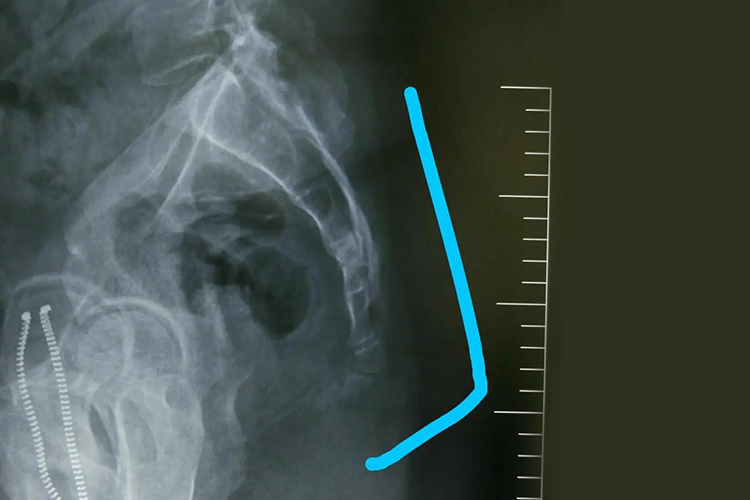

尾骨骨折:尾骨骨折后局部疼痛剧烈,尤其坐位时疼痛加重。检查时局部有明显的压痛,但是肿胀不明显,肛诊时可以触及尾骨的前后错动。尾骨骨折脱位后,由于附着于其上的肛提肌、尾骨肌和肛门外括约肌以及韧带的张力发生变化,患者可出现肛门坠胀感。X线片可以确诊,侧位片可以看到尾骨向前移,正位片上可以见到尾骨的远端向侧方移位。